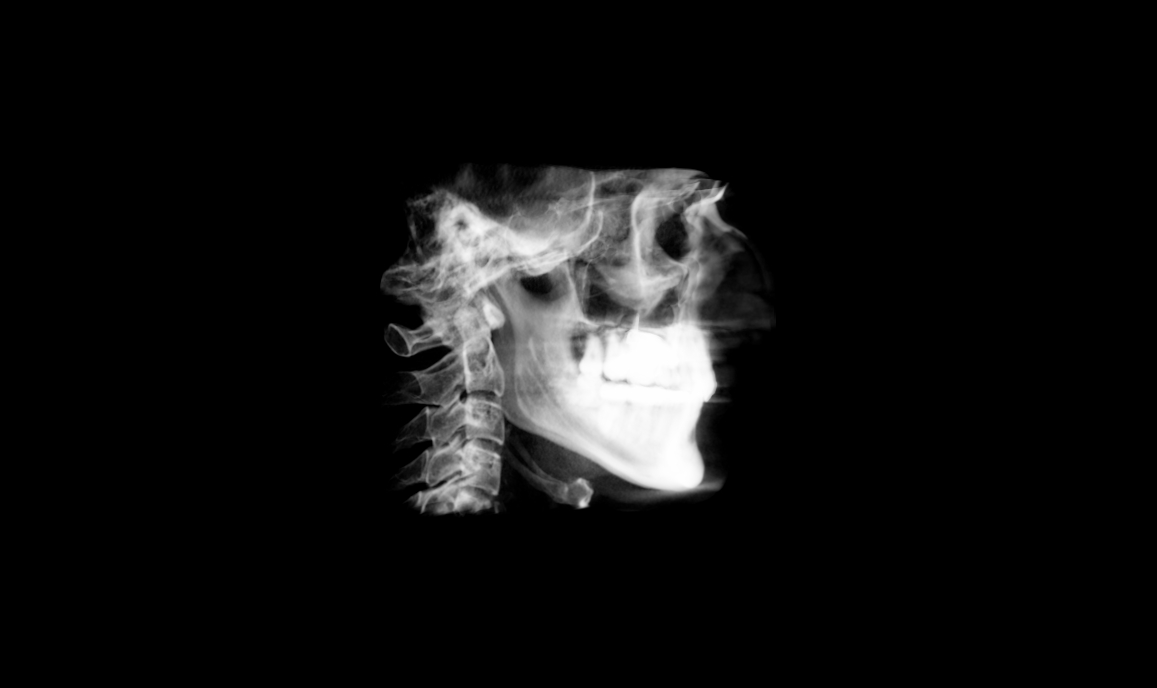

Completed last turn on MARPE on 9th Jan. Total (net, as I went back and forth a bit towards the end) 65 turns = ~5.42mm lateral skeletal expansion of upper jaw going by the device design. IMW (Intermolar width) increased by 7mm from 31 – 38mm.

CBCT:

Note – I’m using 3D Slicer and couldn’t figure out a setting that showed the bone nicely with this one. Possibly because the metal of the expander is much denser so it skews the range. Please send me an email/comment if you know how to get it to render well. I don’t need detail on the expander.